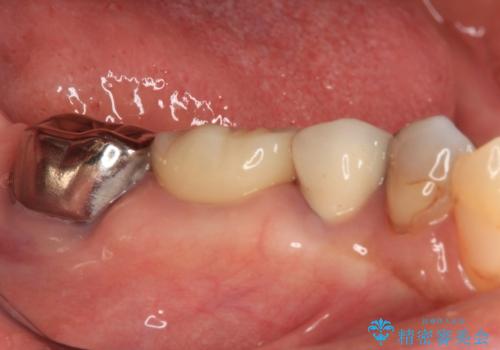

銀歯を外したところ、非常に大きなむし歯が認められましたが、神経組織には及んでおらず、速やかにオールセラミッククラウンによる補綴治療を行いました。